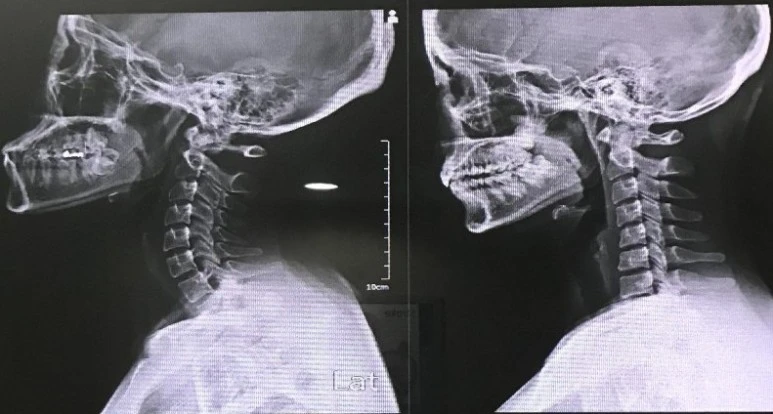

X-ray : 약 3만 원

목디스크, 경추성 두통을 확인하기 위해 엑스레이 사진을 찍었다. 나중에 확인해 보니 경추 3매, 요추 2매, 전척추 2매로 총 7매를 찍었다는 걸 알 수 있었다.

정상적인 사람은 목이 C자 형태인데, 나는 거북목까지는 아니지만 일자목이었다. 일자목이 계속 진행되면 거북목까지 갈 수 있다고 한다. 일자목으로 인해 두통이 올 수도 있지만, 현 상태의 잦아들지 않는 매우 심한 두통의 원인으로 보이진 않았다.

왼쪽이 정상, 오른쪽의 곧은 목뼈가 내 사진이다